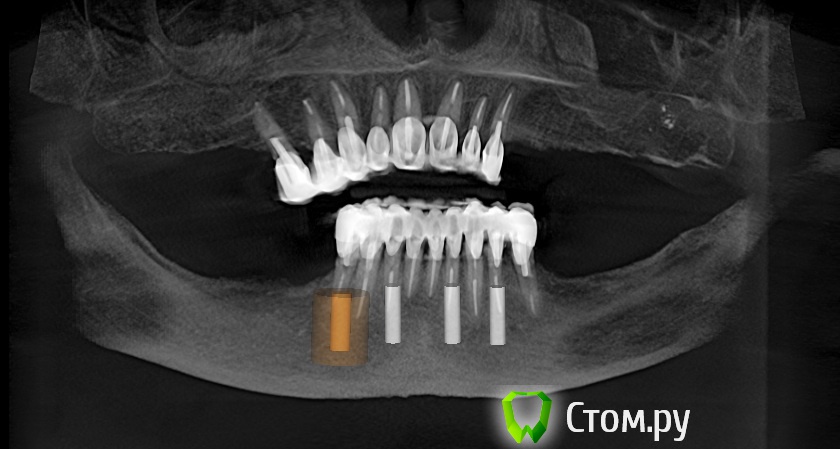

Dr.Sham Опубликовано 14 октября, 2014 Поделиться Опубликовано 14 октября, 2014 (изменено) Планируется удаление всех зубов на НЧ. Пациентка хочет несъемную конструкцию.Вот нарезка.Планируется имплантация Ankylos в позициях 46, 44, 42, 32, 34, 36.В боковых отделах дефицит всего.Думаю удалить зубы через один, чтобы на них временная конструкция держалась, а в промежутках имплантаты.В переднем отделе узко, либо узкие ФДМки, либо заглушка и в овоид край времянок или закрыть свободным трансплантатом.Что думаете?В боковых отделах вопрос...короткие имплантаты и НКР? От сложной костной пластики пациентка отказывается категирочески. Сверху пациентка так же хочет несъем. Поэтому все на 4-х, наверное, не самамя удачная конструкция здесь. Зубы сохранить никак, преп под десной местами по 3 мм. ну и дентин весь мягкий. Изменено 14 октября, 2014 пользователем Dr.Sham Ссылка на комментарий